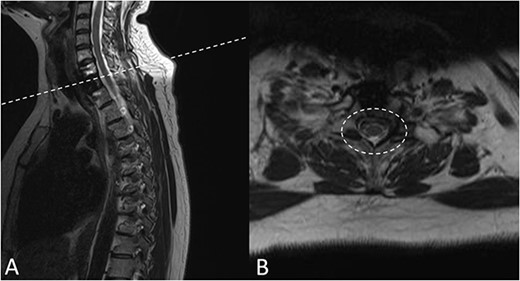

Preoperative magnetic resonance imaging (MRI) and preoperative CT scans helped determine Tokuhashi, Tomita and ESCC scores, which was vital to plan treatment for this patient (Figs 1 and 2). The occurrence of the lesion occurring in T2 indicated an anterior approach. This would be safer than a posterior approach as the ESCC grade of 2 made it surgically challenging to resect tumour and lay instrumentation around the spinal cord. An anterior approach also avoids cervico–thoracic junction fusion.

Preoperative MRI Scan December 2019. (A) Sagittal view of oligometastatic lesion at T2 vertebral body. (B) ESCC grade 2 determined as there is spinal cord compression, but with cerebrospinal fluid visible around the cord.